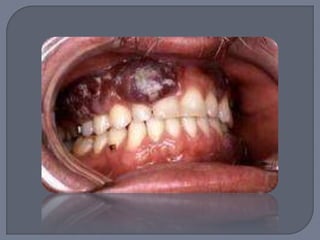

Principal causante virus herpes-8 (HHV-8)

Predisposición genética, infección, influencias

ambientales u desregularización inmunitaria

Cuatro tipos:

1. Tipo clásico:

- Vida adulta tardía

- Hombres italianos y judíos

- Múltiples máculas violáceas y placas en la piel

de las extremidades inferiores

- Crecen lentamente asintomáticas por años

- Lesiones orales raras, en paladar

2. Tipo endémico:

- África

1. Nodular, similar al tipo clásico

2. Agresivo, caracterizado por desarrollo

progresivo de lesiones localmente invasivas

que involucra los tejidos y hueso subyacente.

3. Florido, rápida progresión ampliamente

diseminado, lesiones agresivas con

involucramiento visceral

3. Tipo linfadenopático:

- Gente joven, raza negra

- Crecimiento rápído y generalizado en los

nódulos linfáticos

- Lesiones ocasionales en vísceras e

involucramiento de la piel

4. Tipo iatrogénico:

- Con frecuencia en transplantados de órganos.

Relacionado con el SIDA

 Es necesaria la biopsia

para confirmar

diagnóstico; se puede

utilizar radioterapia,

quimioterapia o escisión

quirúrgica